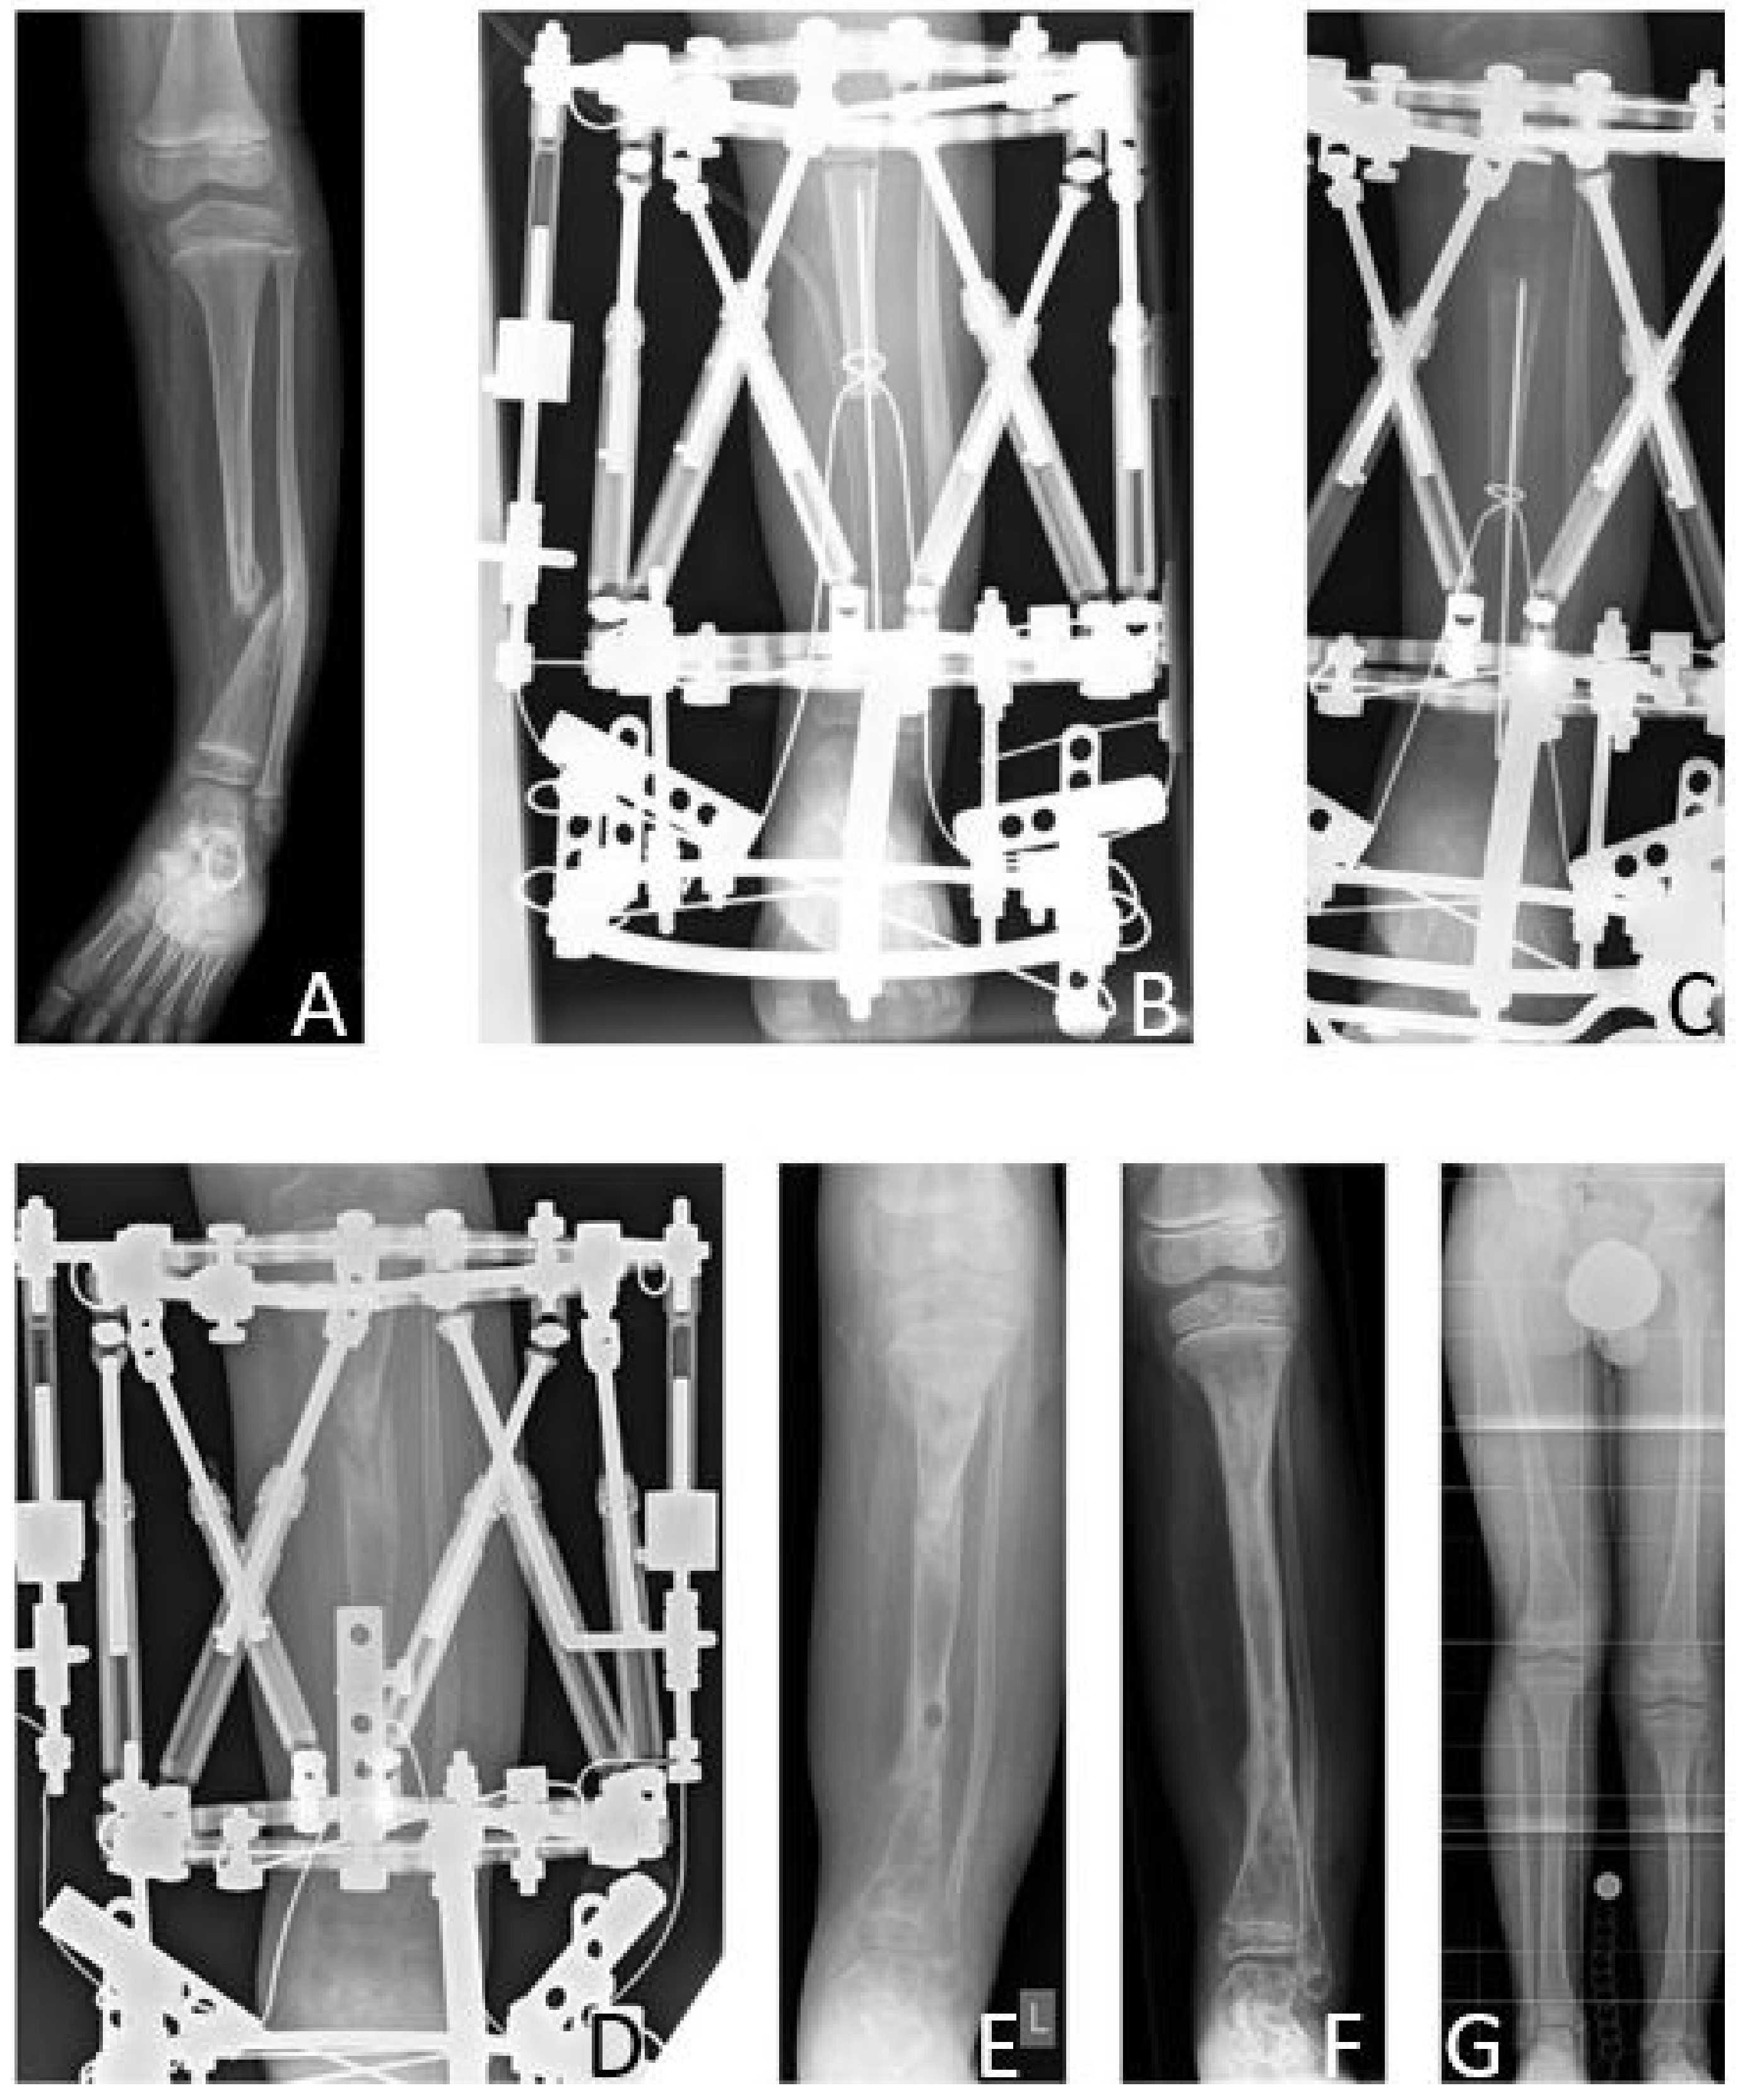

The mean age at first surgery was 7.1 (2.8–14.2) years. Excision of the pseudarthrosis and acute compression before intramedullary stabilization was performed in two cases, while three patients solely received intramedullary nailing for stabilization of the pseudarthrosis site. Four patients (80%) were treated with a Fassier-Duval telescoping nail, and one patient (20%) with a TRIGENTM intramedullary nail. Postoperatively a cast was applied for six weeks. Primary bone union was achieved in three patients (60% primary bone union rate). Excision of the pseudarthrosis had been performed in one of the two cases of failed primary bone union. There were no refractures (0% refracture rate), thus the long-term bone union rate was also 60%. Both patients who failed to achieve primary bone union neither achieved secondary bone union, and showed persistent pseudarthrosis at the time of last follow-up.

According to the modified Johnston criteria, three results were grade 1 and two grade 3 (Figure 8).

Figure 8. Results Group C. Six-month-old female patient with CPT, presenting fracture and pseudarthrosis of the right tibia (A,B). After conservative treatment with orthotic braces, first surgery with resection of the pseudarthrosis and implantation of a Fassier-Duval telescoping nail was performed at the age of four years (C,D). Radiologically, consolidation was achieved 14 months postoperatively (E,F). The patient received subsequent distraction osteogenesis for lengthening of 5 cm when six years old. At the time of last follow-up at the age of nine years she presented a residual LLD of 3.4 cm and ankle valgus (G). (a.p. and lateral views.).